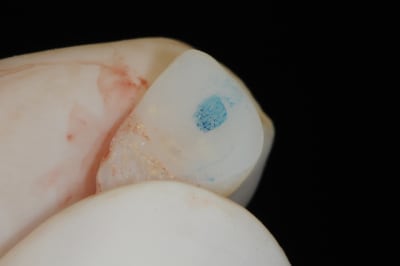

2 -3-4 implant et pilier en place

séquence prothèse:

1-2-3 élaboration de la provisoire sur le pilier définitif et vérification des contacts occlusaux